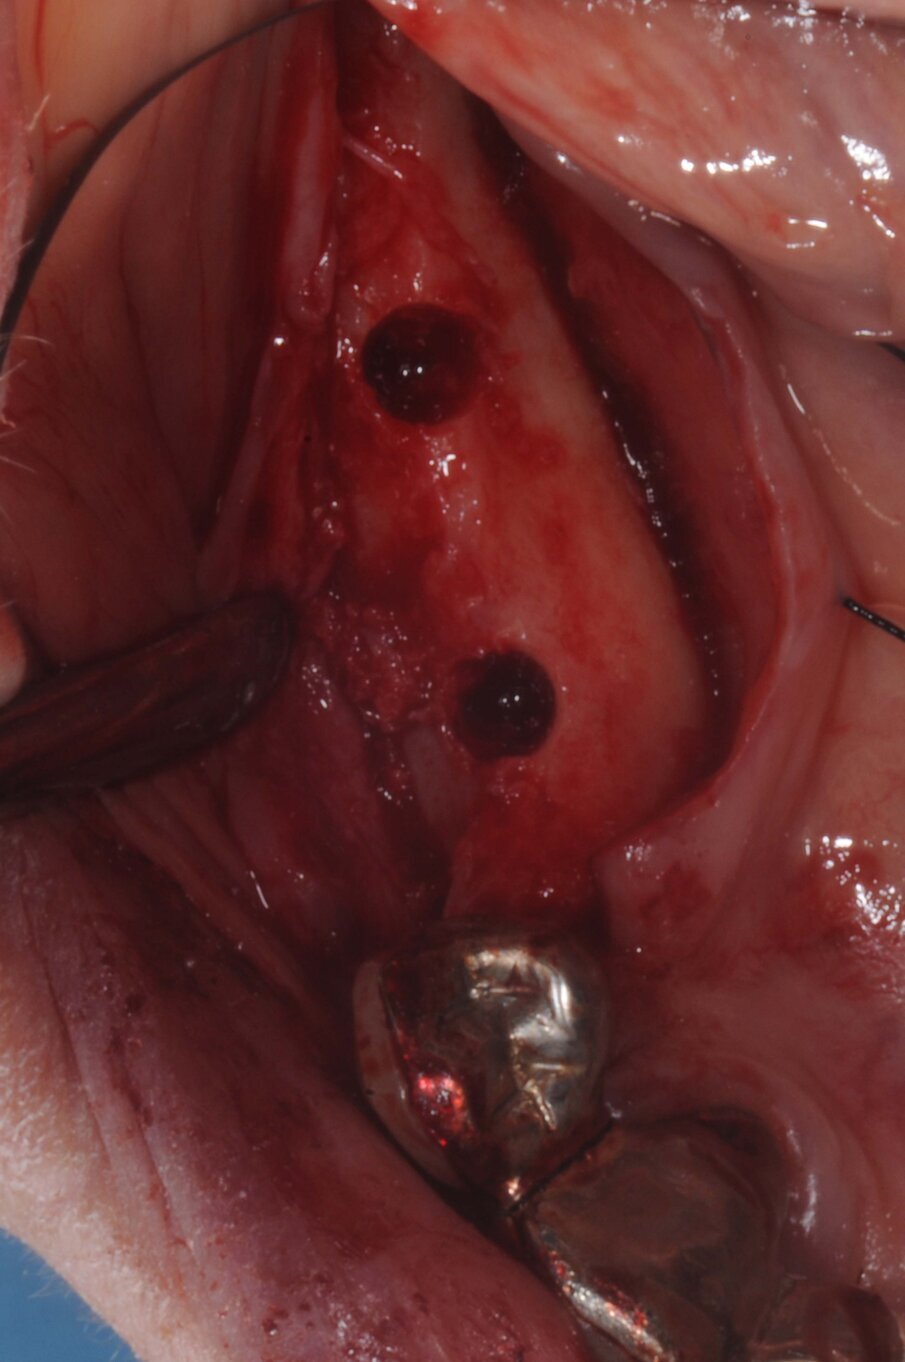

La terapia anticoagulante non è stata interrotta prima della chirurgia ed è stata somministrata la profilassi antibiotica come da protocollo. È stata eseguita un’incisione crestale senza tagli di scarico che è stata estese distalmente fino al trigono retromolare per esporre la branca mandibolare ed avere un sito per raccogliere osso autologo con una fresa carotatrice. Sono state eseguite le osteotomie a basso numero di giri come da protocollo BTI per ottenere un’ulteriore quantità di osso autologo raccolto dalle frese e inseriti due impianti BTI Core 3,75 x 4,5 e 3,5 x 6,5 rispettivamente in posizione 46 e 45.

L’osso autologo è stato mescolato con gel piastrino ottenuto da centrifugazione del sangue del paziente mediante metodica Endoret BTI. La membrana ottenuta è stata applicata a protezione della corticale vestibolare. Ulteriori membrane di gel piastrino sono state applicate sopra l’osso autologo. La stabilita primaria di entrambi gli impianti era superiore ai 50 Newton per cui sono stati avvitati i pilastri Multi-Im e i pilastri di guarigione per un tecnica con una sola chirurgia. Sono state applicate suture sintetiche non riassorbibili a punti staccati (Figg. 3–10). Successivamente è stata eseguita una Rx di controllo. Le suture sono state rimosse a due settimane e la paziente riferì di avere avuto disagi minimi, senza ematomi o edemi estesi e scarsa dolenzia che non richiese l’assunzione di antinfiammatori.